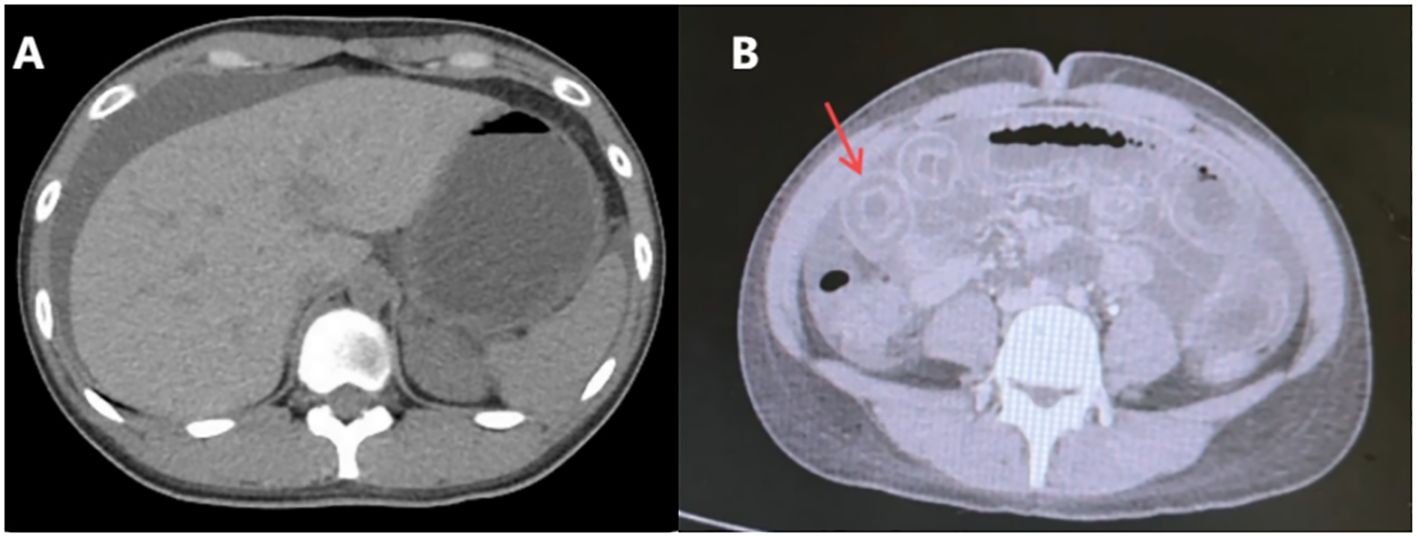

A 27-year-old female with a history of urticaria and tattooing presented to the emergency department with severe upper abdominal colic, which worsened progressively over 4 days following several episodes of watery diarrhea. Initial laboratory tests showed decreased total protein (62.5 g/L) and albumin (31.5 g/L), with mild acid-base and metabolic disturbances. Blood cell counts, serum amylase, lipase, and β-HCG were normal, ruling out pancreatitis, gynecological emergencies, and infectious causes. Abdominal CT revealed slightly disorganized jejunal loops with wall thickening and mild submucosal edema in the horizontal segment of the duodenum (Figures 1A, B). A provisional diagnosis of acute gastroenteritis was made, and the patient received analgesics, proton pump inhibitors, and prophylactic antibiotics, but her pain worsened.

Figure 1. Abdominal computed tomography scan(Aug 28th, 2024). (A) The arrangement of the jejunum in the left upper abdomen is slightly disordered, with thickening of the intestinal wall. (B) Mild submucosal edema in the horizontal segment of the duodenum.